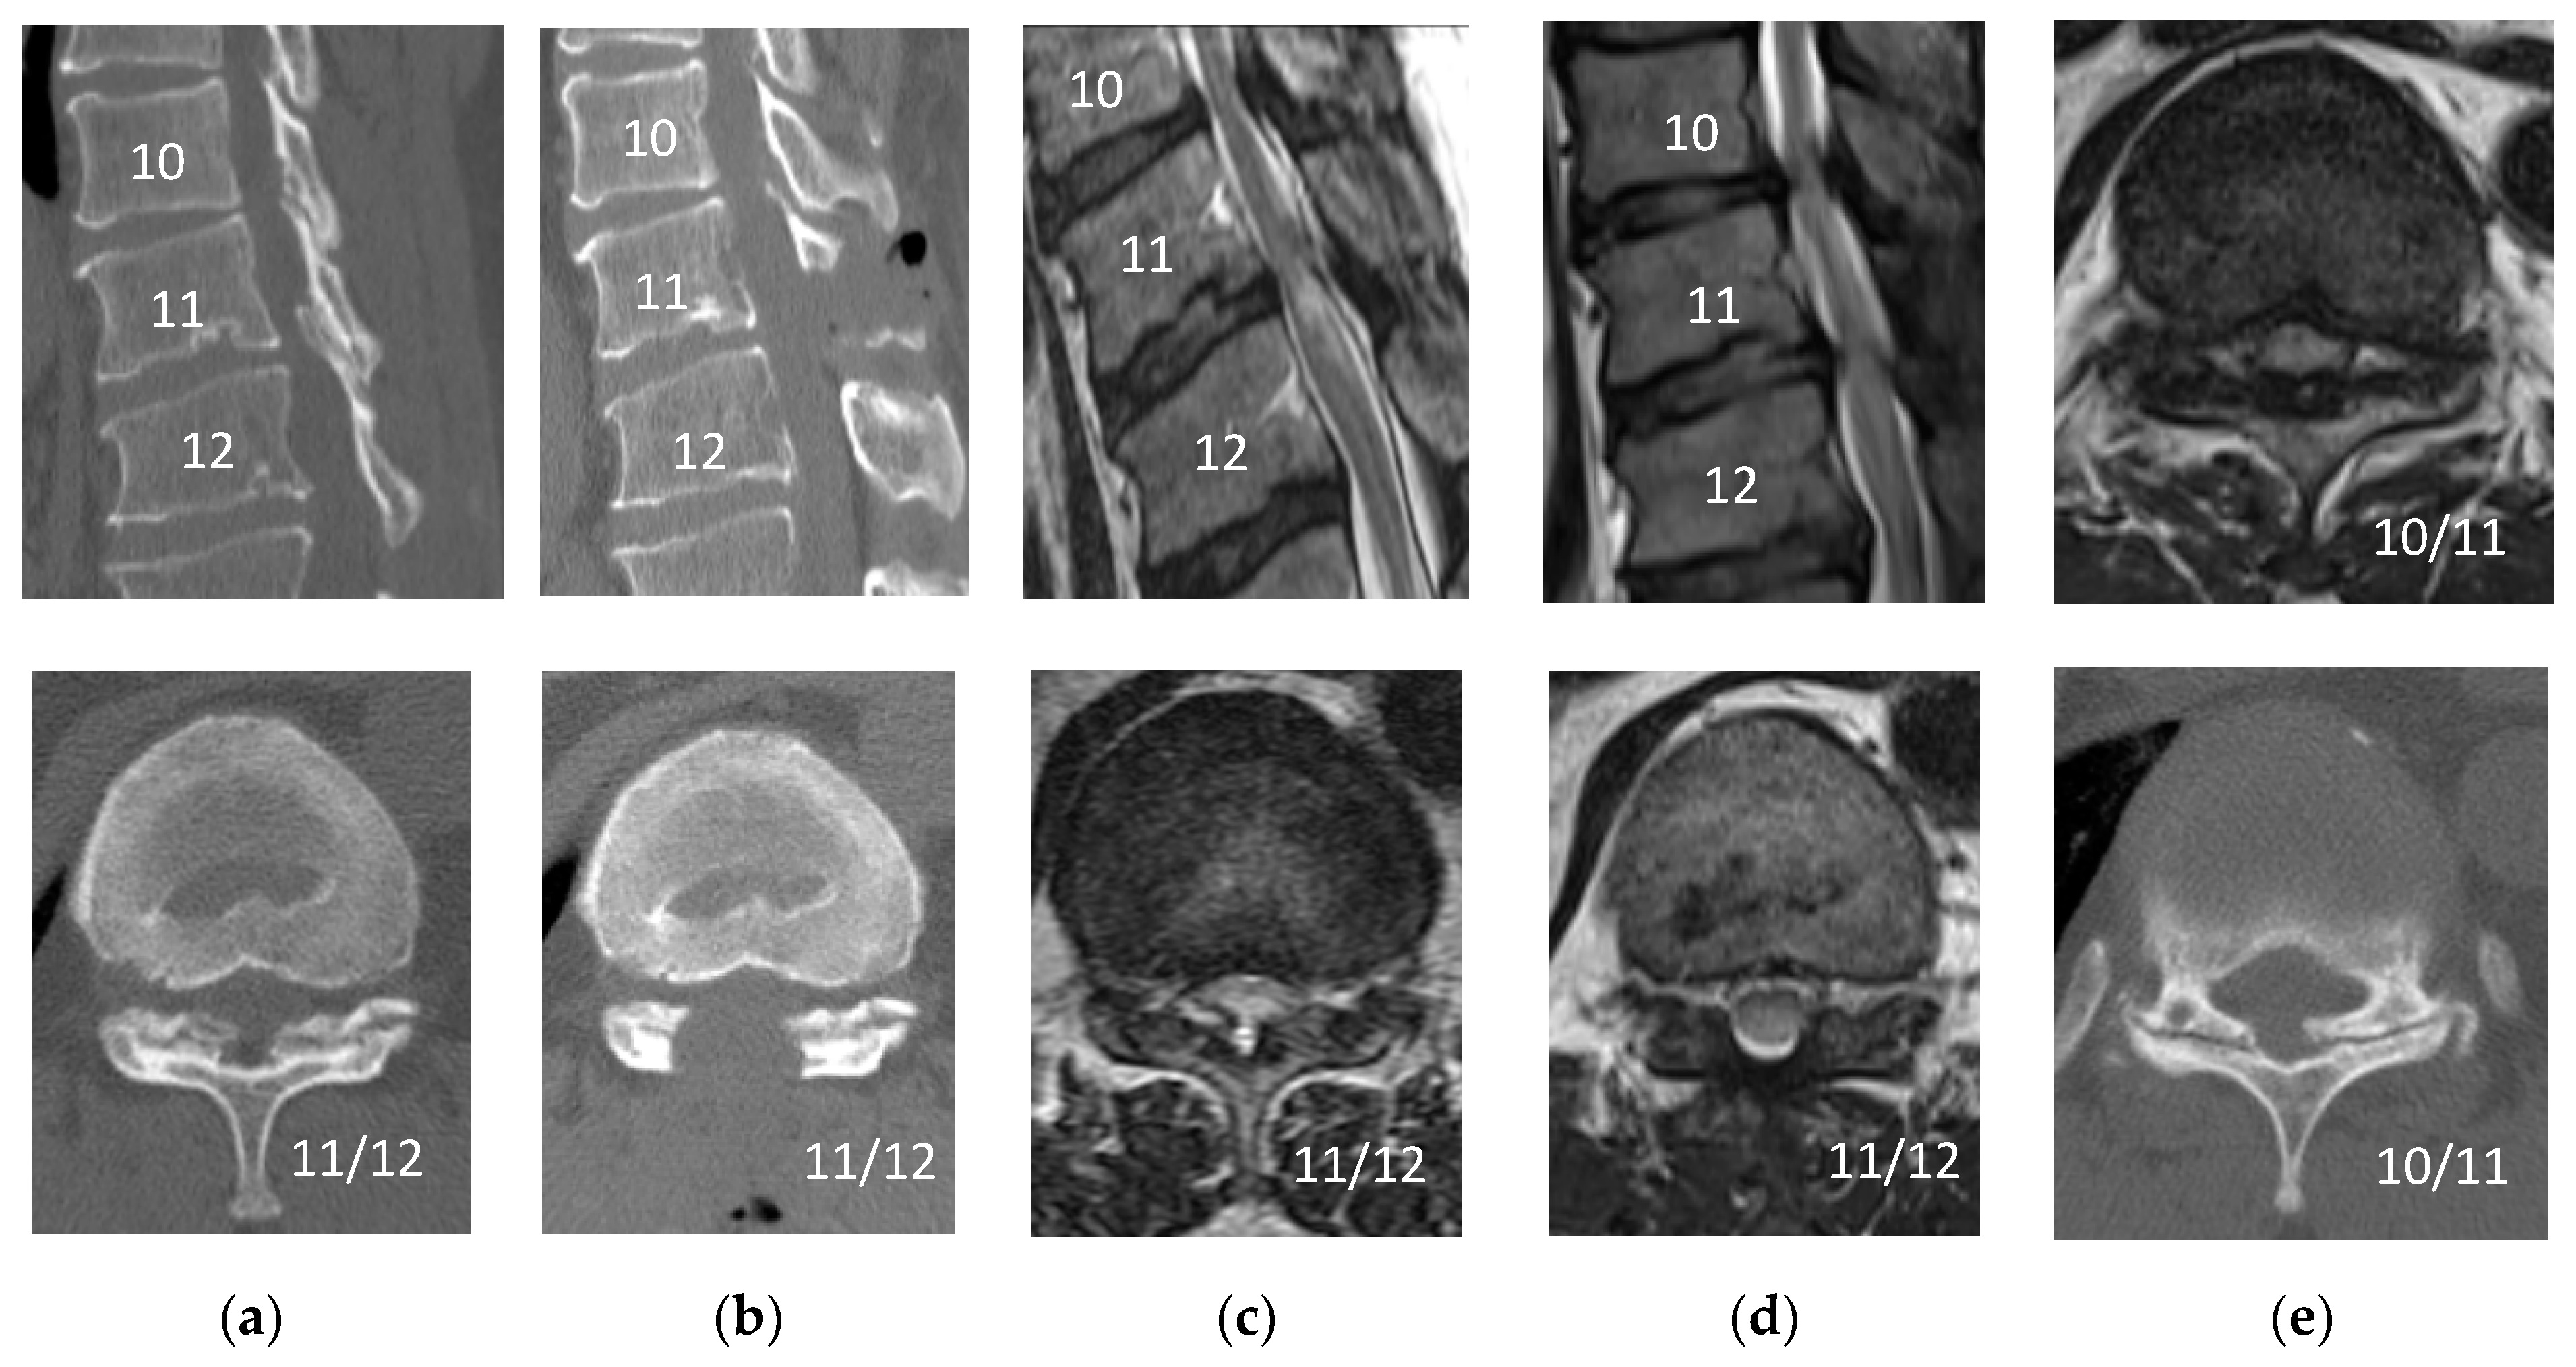

2.2. Surgical Technique